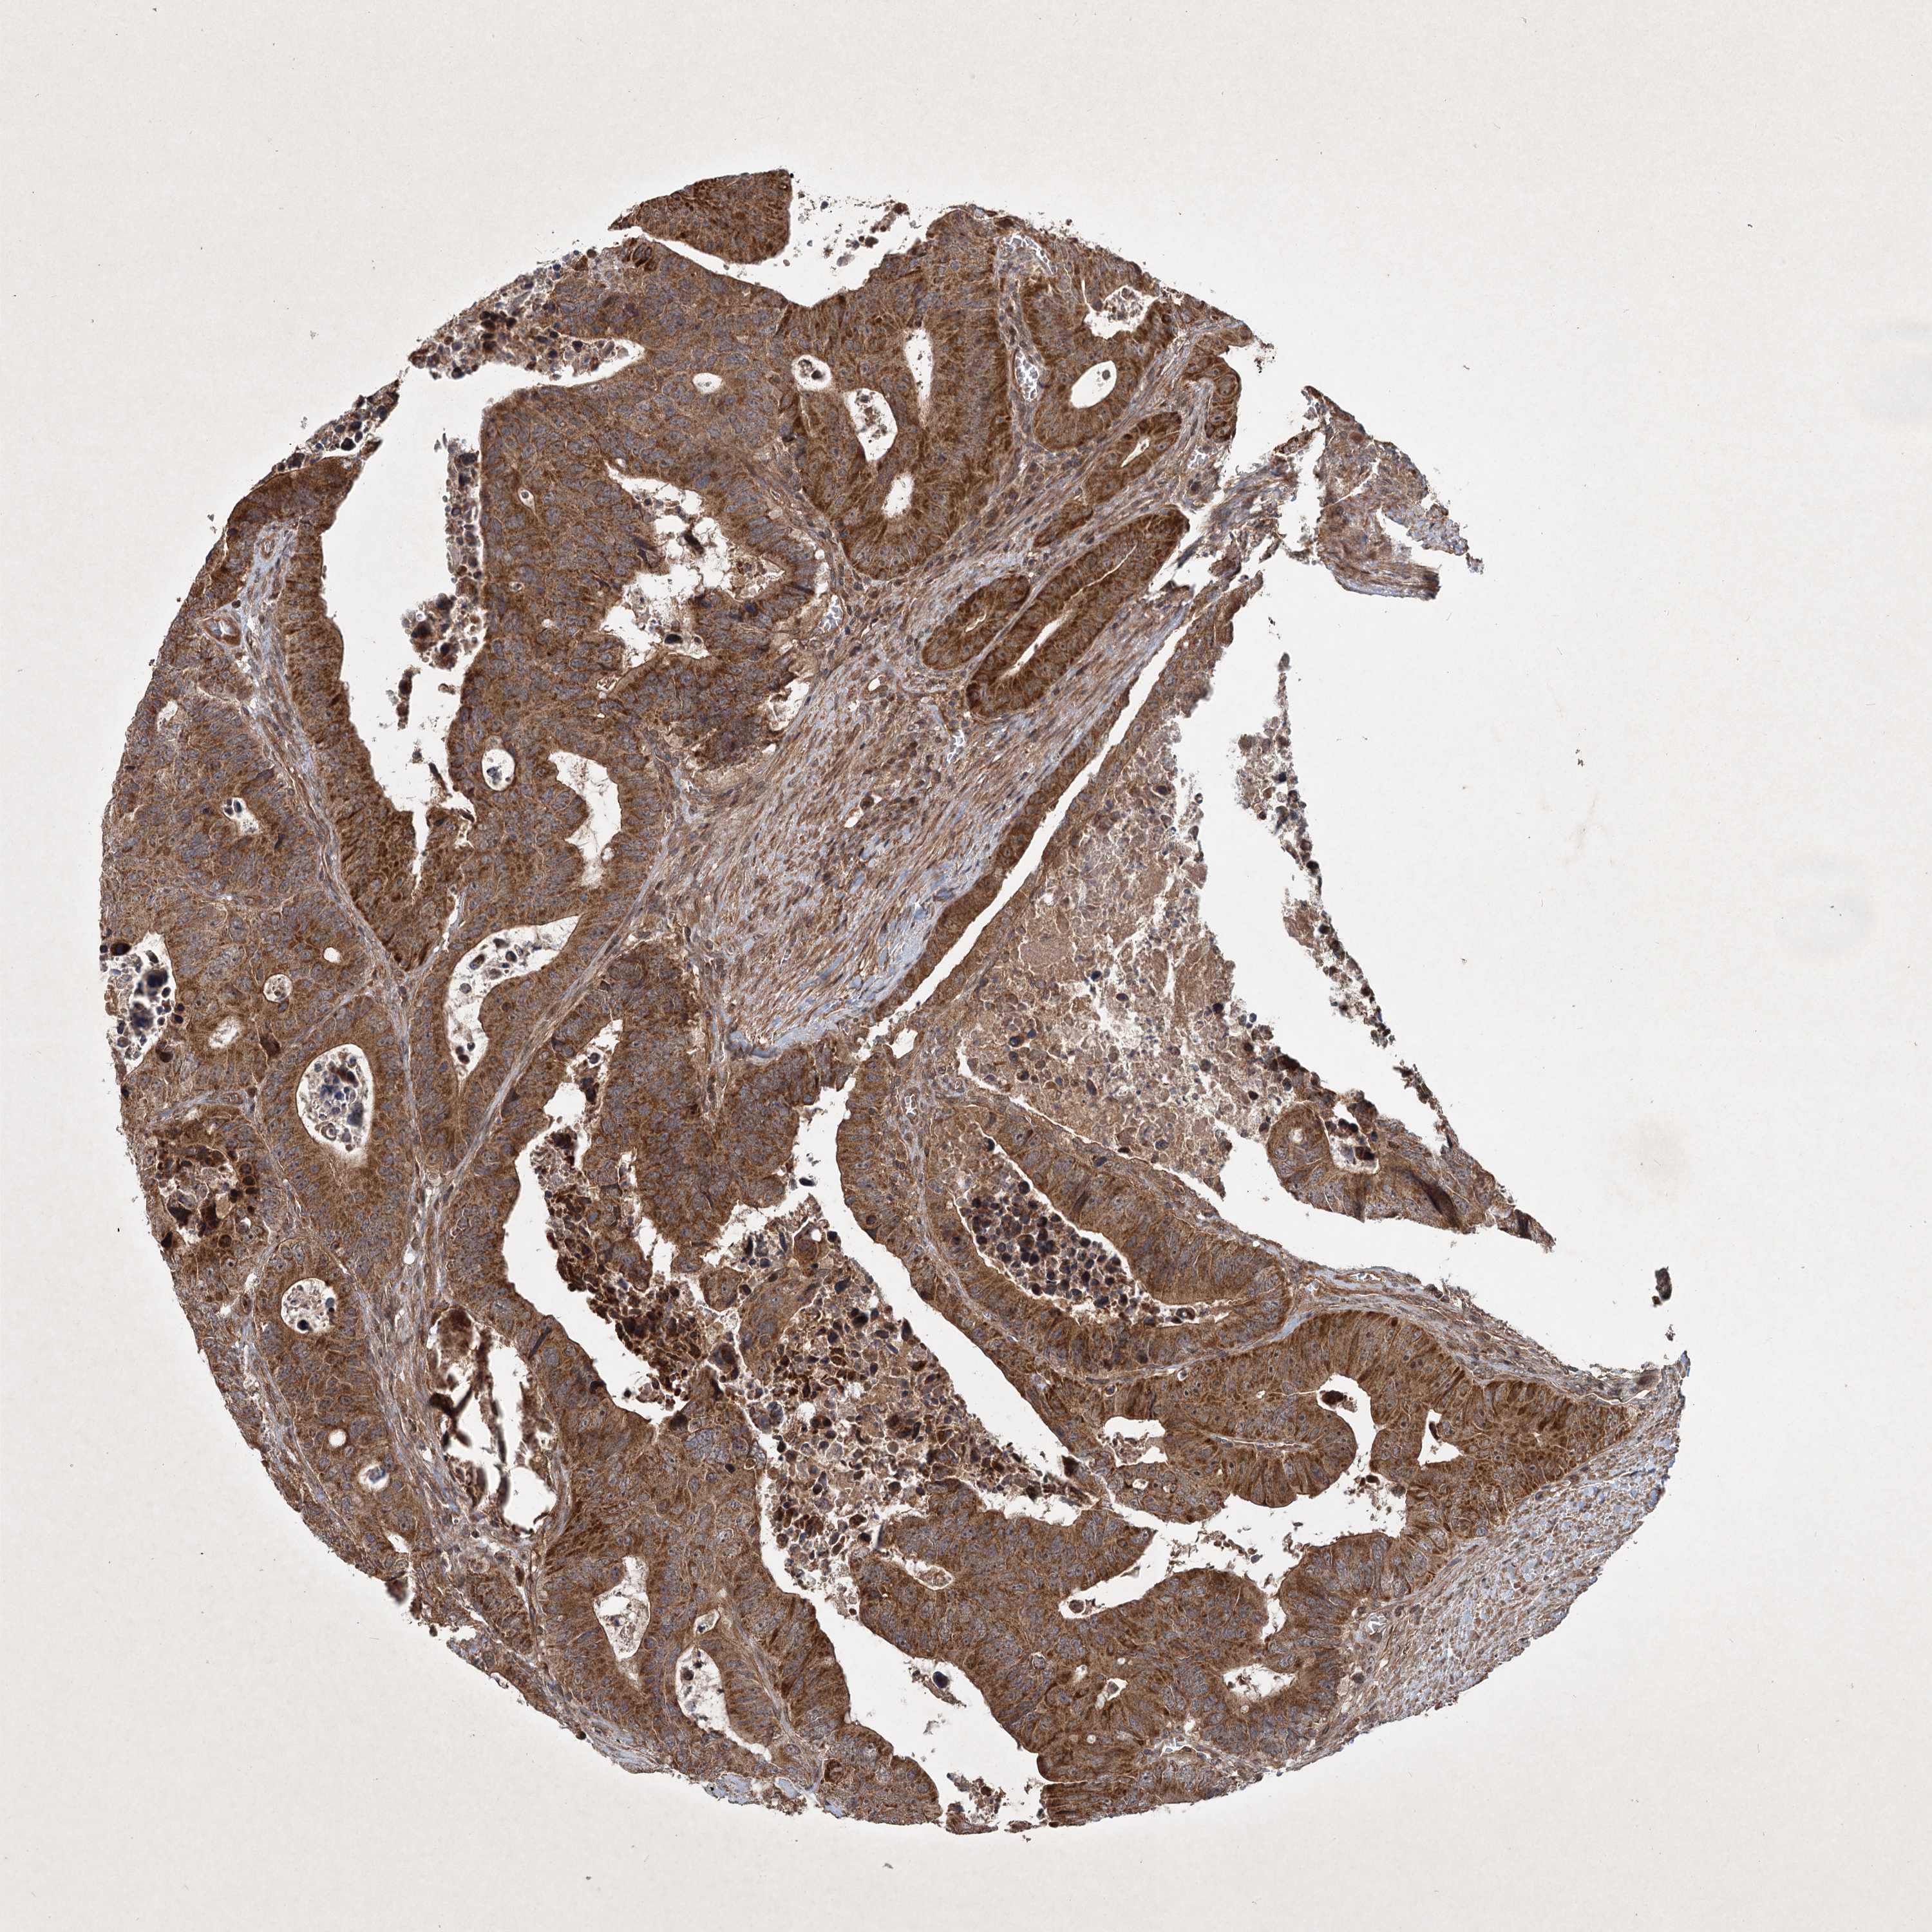

CANCER COLORECTAL CANCER Show tissue menu

Colorectal cancer

Human cancer

Colon adenocarcinoma